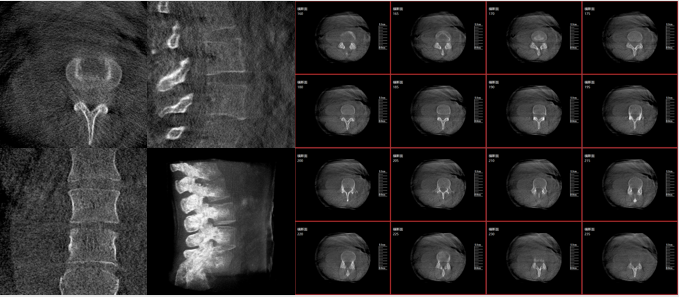

而三維影像的MPR圖像組可以通過(guò)不同平面的切分,使成像區(qū)內(nèi)更豐富的信息得以呈現(xiàn)。尤其是二維影像無(wú)法涉及的橫斷面,提供了另一個(gè)空間維度的信息量。

術(shù)中三維C臂影像